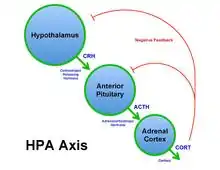

Adrenocorticotropic hormone axis

When a receptor within the body senses a stressor, a signal is sent to the anterior hypothalamus. At the reception of the signal, corticotrophin-releasing factor (CRF) acts on the anterior pituitary. The anterior pituitary in turn releases adrenocorticotropic hormone (ACTH).[13][14] ACTH induces the release of corticosteroids and aldosterone from the adrenal gland. These substances are the main factors responsible for the stress response in humans. Cortisol for example stimulates the mobilization of free fatty acids and proteins and the breakdown of amino acids, and increases serum glucose level and blood pressure,[12] among other effects.[15] On the other hand, aldosterone is responsible for water retention associated with stress. As a result of cells retaining sodium and eliminating potassium, water is retained and blood pressure is increased by increasing the blood volume.